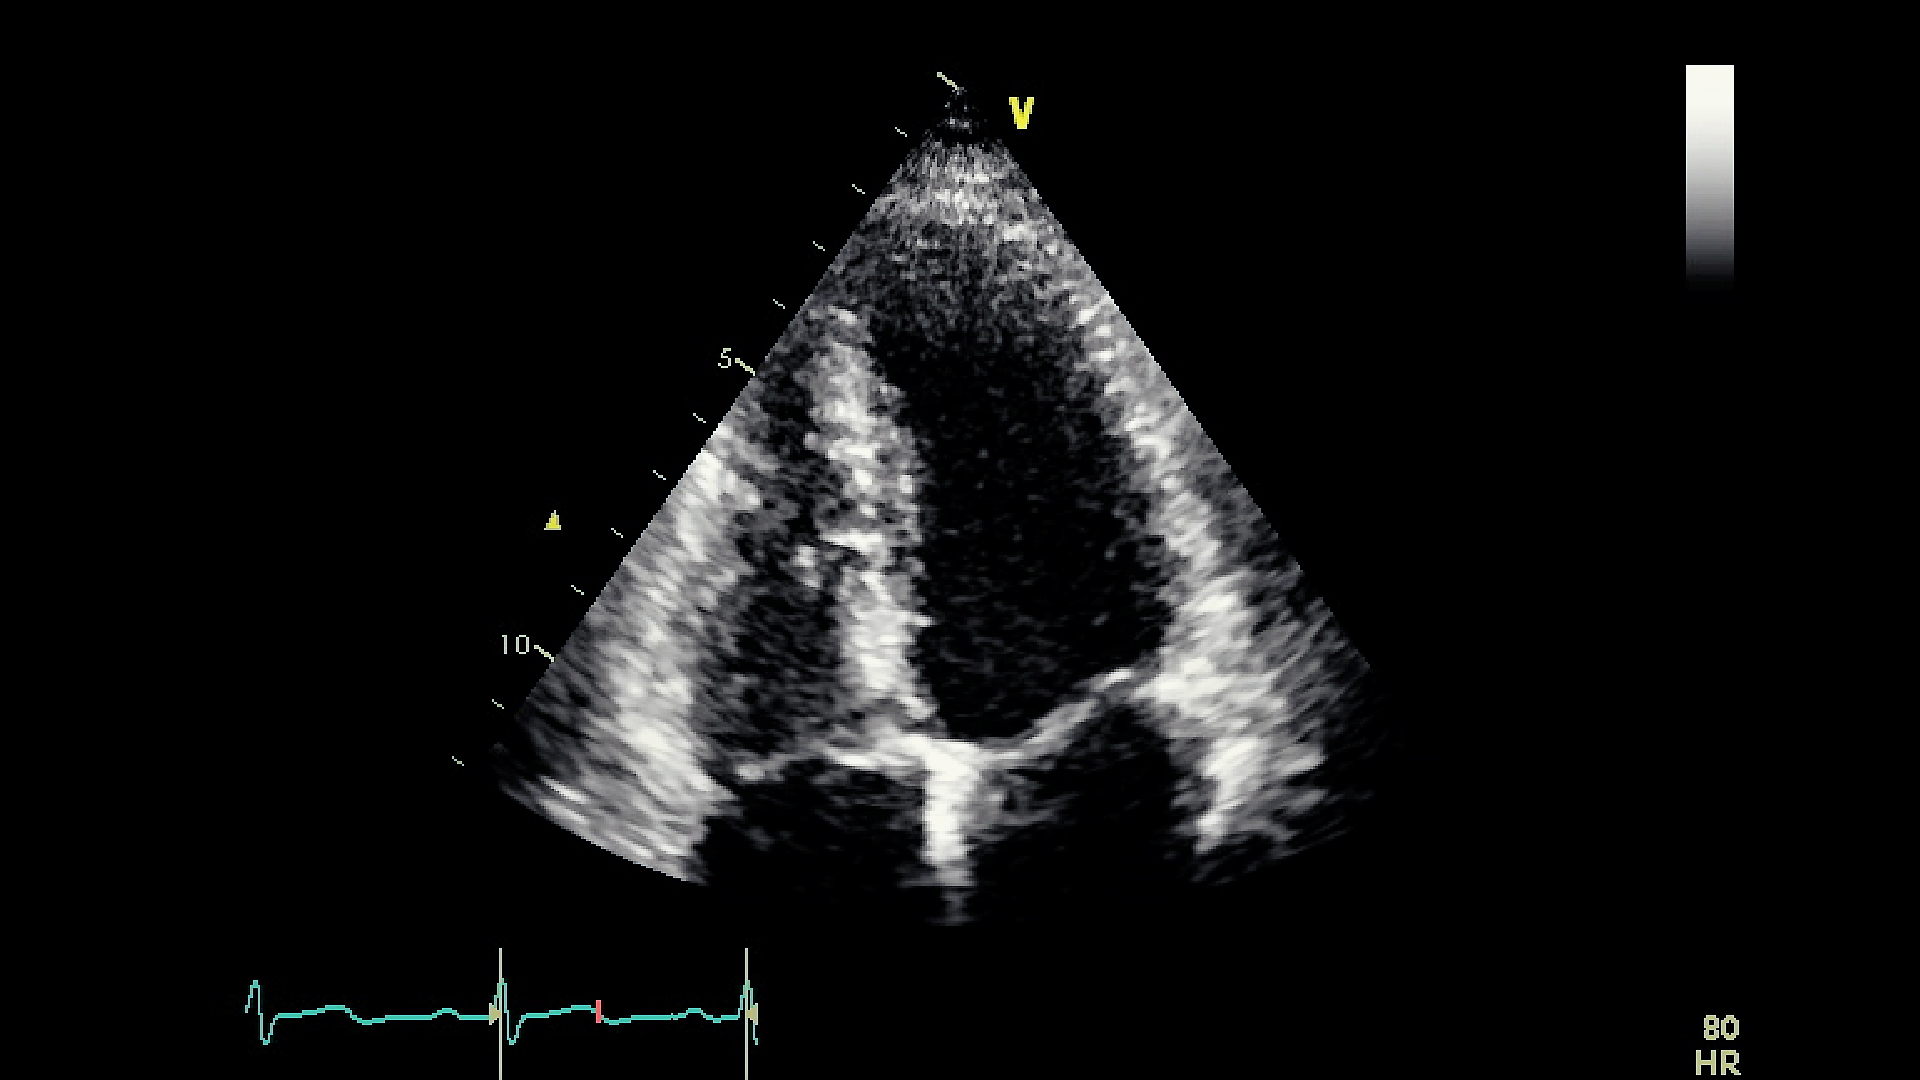

Figure 3 represents captured frames representing the quality of several videos from our dataset, which varies from good to noisy. Figures from 3(a) to 3(f) correspond to distinct frames each captured from different videos. We notice that in Figure 3(a) the left wall of the LV is blurred. Also, in Figure 3(b), the left wall of the LV is blurred and almost missing. In the same way, we observe that the totality of the LV wall is blurred in Figure 3(c); and that the interior of the LV is disrupted with noise in Figure 3(d). Finally, both Figure 3(e) and Figure 3(f) show acceptable LV representations, where the LV walls are captured and the chamber’s interior is empty from noise. Moreover, since our study is centered on the LV chamber only, we purposely ignore the distortions of the rest of the cardiac chambers (Right Ventricle, Left Atrium, and Right Atrium) in the dataset videos. For example, in Figure 3(e), both the Left Atrium and the Right Atrium are partially cut from the view, however, this does not impact our study.

Refer to caption

(a)

(b)

(c)

(d)

(e)

(f)

Figure 3: Captured frames from 6 different videos of our dataset, where each image from 3(a) to 3(f) corresponds to a distinct video. 3(a) represents a blurred left wall in the LV, 3(b) represents a missing left wall in the LV, 3(c) represents blurred LV walls, 3(d) represents noise inside the LV, and 3(e) and 3(f) represent normal echocardiograms

Hence, our final set of videos for segmentation consists of both clear and blurred video images of the LV chamber.